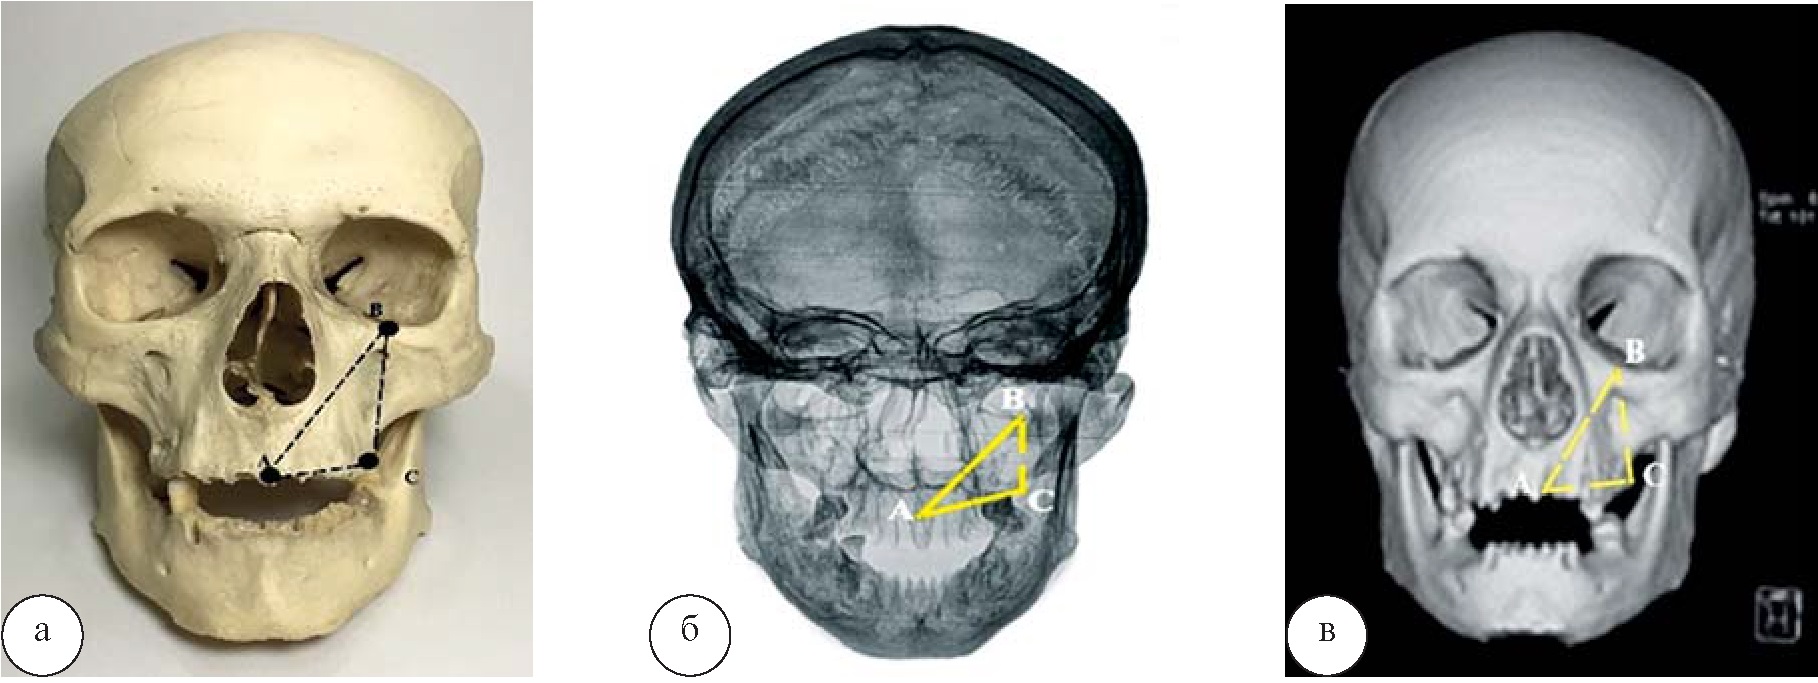

Результаты и их обсуждение. Установлены статистически значимые различия между показателями, полученными на анатомическом препарате и на рентгенограмме черепа. Данные, полученные при измерениях на черепе и СКТ, практически совпадают (рис. 2, табл. 1).

Рис. 2. Проекционный передний верхнечелюстной треугольник: а – череп; б – рентгенограмма; в – СКТ